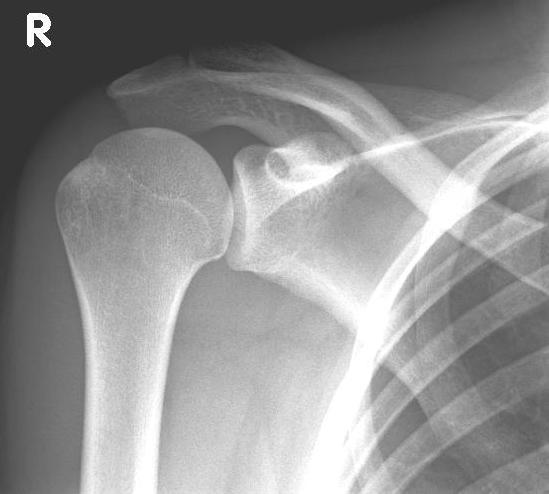

left: X-ray image of an omarthrosis

right: X-ray of a healthy shoulder joint

Diagnostics

Clinical examination often reveals a painful restriction of shoulder movement. A reduction in strength of the shoulder or arm is also frequently detectable. Friction phenomena, so-called "crepitations", are conspicuous on examination.

X-rays can be used to reliably diagnose the extent of joint wear. In the case of severe osteoarthritis, for example, the joint space and the formation of jagged edges (osteophytes) can be detected. If additional damage to the tendons of the shoulder (rotator cuff) is suspected, ultrasound examination (sonography) or magnetic resonance imaging (MRI) can help clarify the situation.